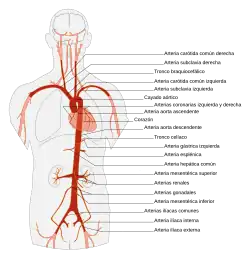

La aorta es la principal arteria del cuerpo humano,[1] midiendo hasta 2,5 cm de diámetro (a la altura del diafragma) en adultos.[2] Se origina en el ventrículo izquierdo del corazón, su trayecto inicial es ascendente, posteriormente forma un arco llamado arco aórtico y desciende atravesando el tórax hasta llegar al abdomen, donde se divide en las 2 ilíacas comunes que se dirigen a los miembros inferiores.[3] Transporta y distribuye sangre rica en oxígeno y da origen a todas las arterias del sistema circulatorio excepto las arterias pulmonares que nacen en el ventrículo derecho del corazón.[4]

La aorta se divide en tres partes: aorta ascendente, arco aórtico o cayado aórtico y aorta descendente. Esta última se divide en dos partes separadas por el diafragma que se llaman aorta torácica y aorta abdominal.

La aorta y sus ramas

La aorta ascendente emite dos ramas, las arterias coronarias, que distribuyen sangre en el miocardio. Luego, gira hacia el lado izquierdo del cuerpo, donde forma el cayado de la aorta (arco aórtico), el cual desciende y termina a nivel del disco intervertebral que separa la cuarta y la quinta vértebra dorsal.

Al continuar su descenso se convierte en aorta descendente, se aproxima a los cuerpos vertebrales, cruza el diafragma, atraviesa el abdomen, y se divide, a la altura de la cuarta vértebra lumbar en las arterias ilíacas primitivas, que llevan sangre a los miembros inferiores. A lo largo de su recorrido emite vasos que se ramifican en otros más pequeños que distribuyen la sangre en los distintos órganos. En estos, las arterias se dividen en arteriolas, y después en capilares, que irrigan todos los tejidos del cuerpo, excepto los alveolos pulmonares.

- Ramas de la porción ascendente: arterias coronarias.

- Ramas del cayado de la aorta (arco aórtico): tronco braquiocefálico, arteria carótida común izquierda y arteria subclavia izquierda.

- Ramas de la porción descendente.

- Ramas de la porción descendente torácica: arterias bronquiales, arterias esofágicas, ramas mediastínicas de la aorta torácica y arterias intercostales posteriores.

- Ramas de la porción descendente abdominal:

- Ramas parietales: arteria diafragmática inferior y arterias lumbares;

- Ramas viscerales: tronco celíaco, arteria mesentérica superior, arteria suprarrenal media, arteria renal, arterias gonadales (arteria ovárica/arteria testicular), y arteria mesentérica inferior.

- Ramas terminales: arteria sacra media, arterias ilíacas primitivas derecha e izquierda.[12]